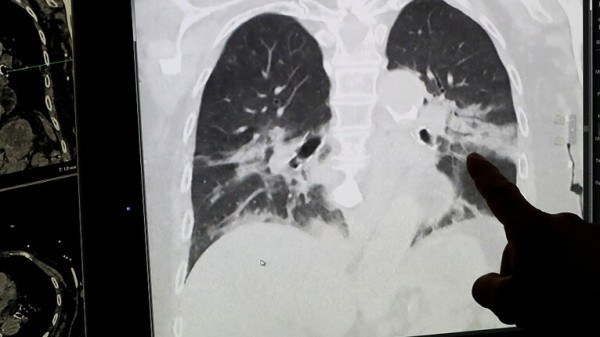

مع دخول تونس الموجة الثانية من الإصابات بفيروس كورونا، صمم فريق من المطورين برنامجا يستخدم تقنية الذكاء الاصطناعي لرصد أعراض مرض كوفيد-19 في الرئة.

وبحسب (رويترز) يعمل البرنامج عن طريق مقارنة الأشعة السينية لرئة مريض بأشعة المشتبه في إصابته بالمرض وتحدد الحلول الحسابية بعد ذلك ما إذا كان المشتبه في إصابته مصابا بالفعل بدقة تصل إلى 92%.

وتمت تغذية البرنامج بعشرات الآلاف من الصور الرئوية من مستشفيات في الصين وإيطاليا وإسبانيا لتعزيز قاعدة بياناته وتقوية قدرته على المقارنة.